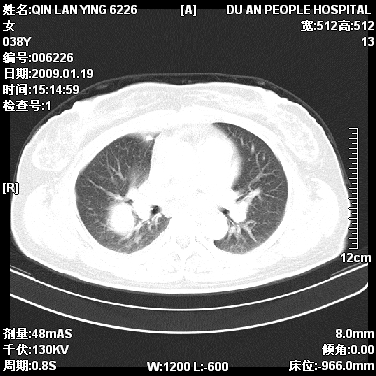

女,38岁,胸疼1个月。wbc:1万4

1)右肺中央型肺癌并右肺上叶阻塞性肺炎、节段性肺不张,纵隔淋巴结转移、右侧胸膜转移、肝脏转移。2)右侧胸腔少量积液。

1、右侧中央型肺癌并阻塞性肺不张,纵隔内、主动脉弓旁、右肺门淋巴结及肝脏转移可能性大,建议纤支镜进一步检查。

2、右侧胸腔积液。

本病例有几个容易诊断的地方:1、右肺上叶前段支气管闭塞,肺不张。2、淋巴结明显肿大。3、肝脏多个类圆形低密度影呈“牛眼征”改变,高度提示转移。

从影像学角度分析      右肺上叶中央型肺癌,并阻塞性不张、肺炎,纵隔淋巴结、膈顶淋巴结转移。

肝内两个大小不等低密度结节,内可见更低密度影,首先考虑肝内转移瘤,但联想到患者wbc1万4,建议楼主还是做个增强比较明确,除外肝脓肿的可能。